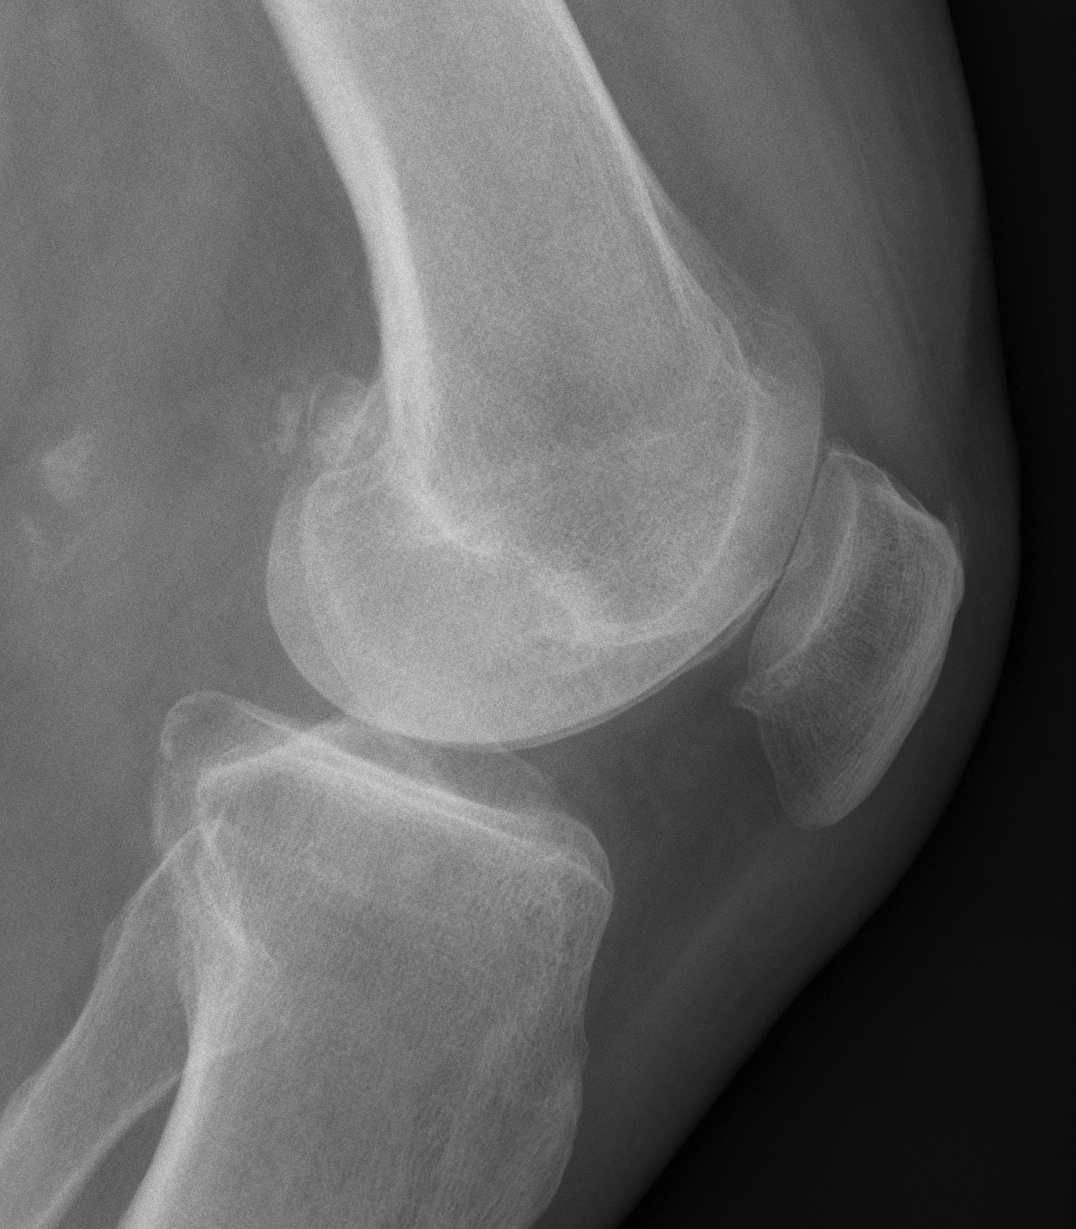

Patient 1